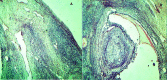

Growth differentiation factor 9 (GDF9) plays a critical role in ovarian follicular development and ovulation rate. The present study aimed to investigate the correlation between the single-nucleotide polymorphism (SNP) of the GDF9 gene and reproductive performance variables, such as fertility and sterility in Awassi sheep. Forty pairs of ovaries from a total of 40 slaughtered Iraqi Awassi ewes were used in this study. Twenty of the ovaries were collected from sterile ewes and the other 20 ovaries were taken from fertile ewes for genomic DNA extraction, polymerase chain reaction, and sequencing to detect GDF9 gene polymorphism. Follicles and oocytes of all the 40 ovaries were evaluated and compared with the results of genotyping. Furthermore, histopathological and microscopic evaluations were performed for 40 ovarian tissues of the two groups. The sequence analysis revealed that exon I had three SNPs, including T(114)C, G(129)R, and G(199)A. The first two SNPs were silent mutations and the last mutation was missense responsible for the substitution of glutamic acid with lysine at position 67. The current study showed a significant increase (P≤0.01) in GG, AA, CC, GA, and GG genotypes at G(129)R, G(199)A, T(114)C, G(129)R, and G(199)A loci, respectively. Moreover, the TT genotype in locus T(114)C was recorded to significantly augment (P≤0.05) in the fertile ewes. Mutant GA genotype of the G(129)R locus led to a significant (P≤0.05) increase in the percentage of follicles (4-8 mm) and oocytes number, compared to wild GG. On the other hand, a significant decrease was recorded in the mutant AA genotype in G(199)A, compared to wild GG. Differences between CC and TT genotypes at T(114)C locus were not significant. Histopathological examination revealed hypoplasia in the ovarian tissue of sterile ewes accompanied by fibrous connective tissue invasion and follicles degeneration. However, in the fertile ewes, the ovarian tissues were normal with the presence of numerous corpus albicans and degenerative corpus luteum. According to the findings of this study, the homozygote mutation in fertile ewes minimized the number of follicles and oocytes leading to sterility, while the heterozygote mutation was reported in the fertile Awassi ewes.